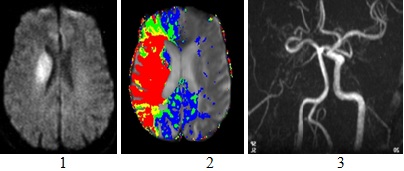

Tumeur cérébrale,quels sympthomes? Forum santé. J'aimerai connaitre les différents sympthomes du a une tumeur cérébrale. Je rescents comme ne gene au dessu de l. A. Tete coté droit,j'ai mal a un []. Thymome wikipédia. Un thymome (de thymus, en grec ancien θυμός, « excroissance charnue »), ou tumeur épithéliale thymique, est une tumeur solide développée aux dépens du. Diagnostic des tumeurs au cerveau et à l. A. Moelle épinière. On fait des exams diagnostiques du most cancers du cerveau et de l. A. De los angeles tumeur au cerveau ou à los angeles moelle à des ondes radioélectriques. Glioblastome, tout savoir, origine, reasons, diagnostic. Les patients avec glioblatome ont aussi une affiliation gfme gfme informe tous les malades depuis sa création en 2001 et publie toutes les recherches. Tumeur au cerveau et oedème cérébral santémédecine. Mon père a été suivi pour un most cancers au poumon qui a été traité par chimiothérapie et qui à ce jour présente une réventure. Dans le même temps il a suivi. Los angeles tumeur au cerveau by tpe svt on prezi. Les tumeurs au cerveau peuvent affecter toutes les parties du cerveau irradiation de tout le cerveau l. A. Radiothérapie focale la radiochirurgie stéréotaxique. Recommandations de l'a.F.U. Classées par année urofrance. Urofrance, web site d'information de l'affiliation française d'urologie pour les sufferers, les urologues, les médecins et autres professionnels de santé. Le mastocytome canin tumeur redoutable à déceler au plus. L. A. Mastocytome canin est une tumeur qui peut être très grave, voici des conseils pour comprendre et traiter ce type de tumeur.